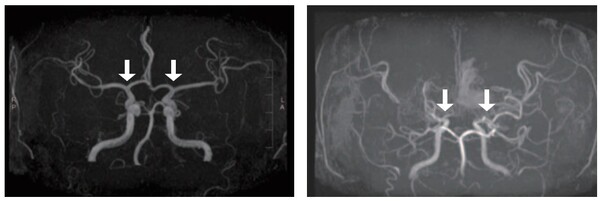

![[사진 왼쪽부터] 정상 및 모야모야병 환자의 뇌혈관](https://cdn.healthlifeherald.com/news/photo/202507/2851_4866_4625.jpg)

모야모야병은 내경동맥이 점차 좁아지면서 뇌혈류가 부족해지고, 이를 보완하려는 비정상적 혈관이 형성되는 질환이다. 이로 인해 뇌출혈이나 뇌경색과 같은 심각한 합병증이 발생하며, 특히 소아에서 조기 진단이 어렵고 기존의 침습적 진단법은 부담이 크다는 한계가 있었다. 이번 연구는 이러한 문제점을 극복할 수 있는 비침습적 대안을 제시했다는 데 의미가 크다.